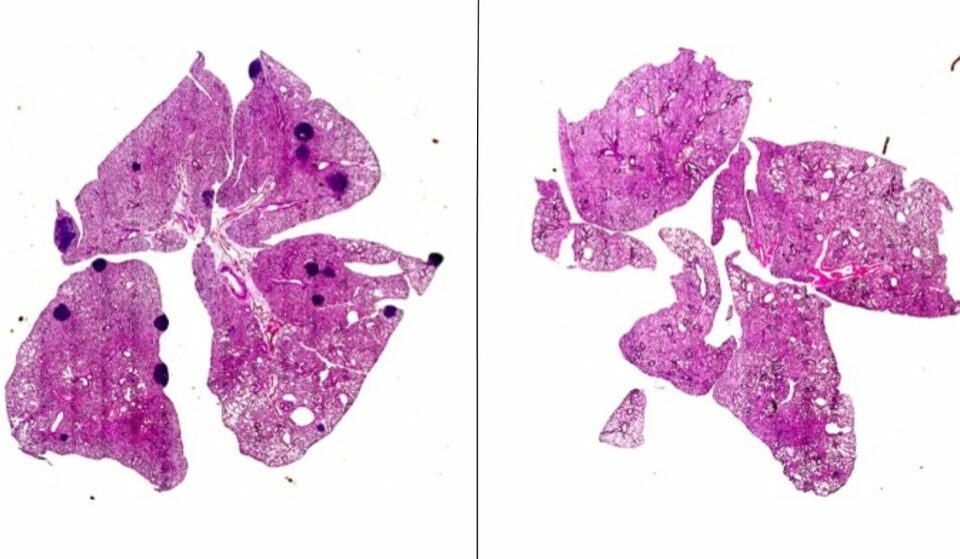

Aspirin, a new ally against cancer: metastasis is stopped in a novel experiment with mice

This common drug can prevent T cells from being inhibited, improving their ability to destroy cancer cells. Ángel Lanas, scientific director of the IIS Aragón, explains this to Science Media Centre.